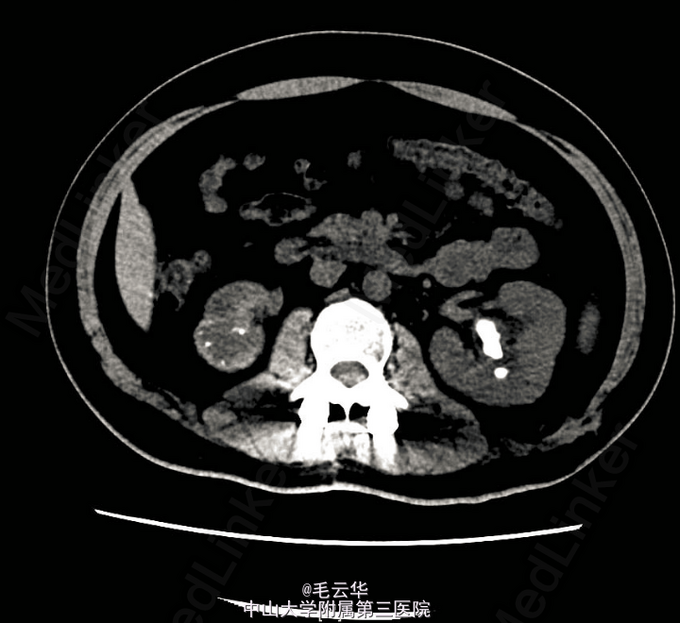

入院诊断:附睾输精管结核,肾结核,肺结核 入院后完善相关检查,尿常规:WBC 232个/ul,RBC 14个/ul。尿抗酸杆菌阴性。CRP阴性,PPD试验阴性。膀胱镜检精阜及后尿道充血明显,余未见异常。胸片未见异常。双肾CTU示右肾、右输尿管结石,右肾萎缩并功能功能重度减退减退,未除外肾结核。带抗结核药(异烟肼、利福平、吡嗪酰胺三联)出院。口服抗结核药治疗2周后返院行腹腔镜下右肾右输尿管切除术。术后继续抗结核治疗。